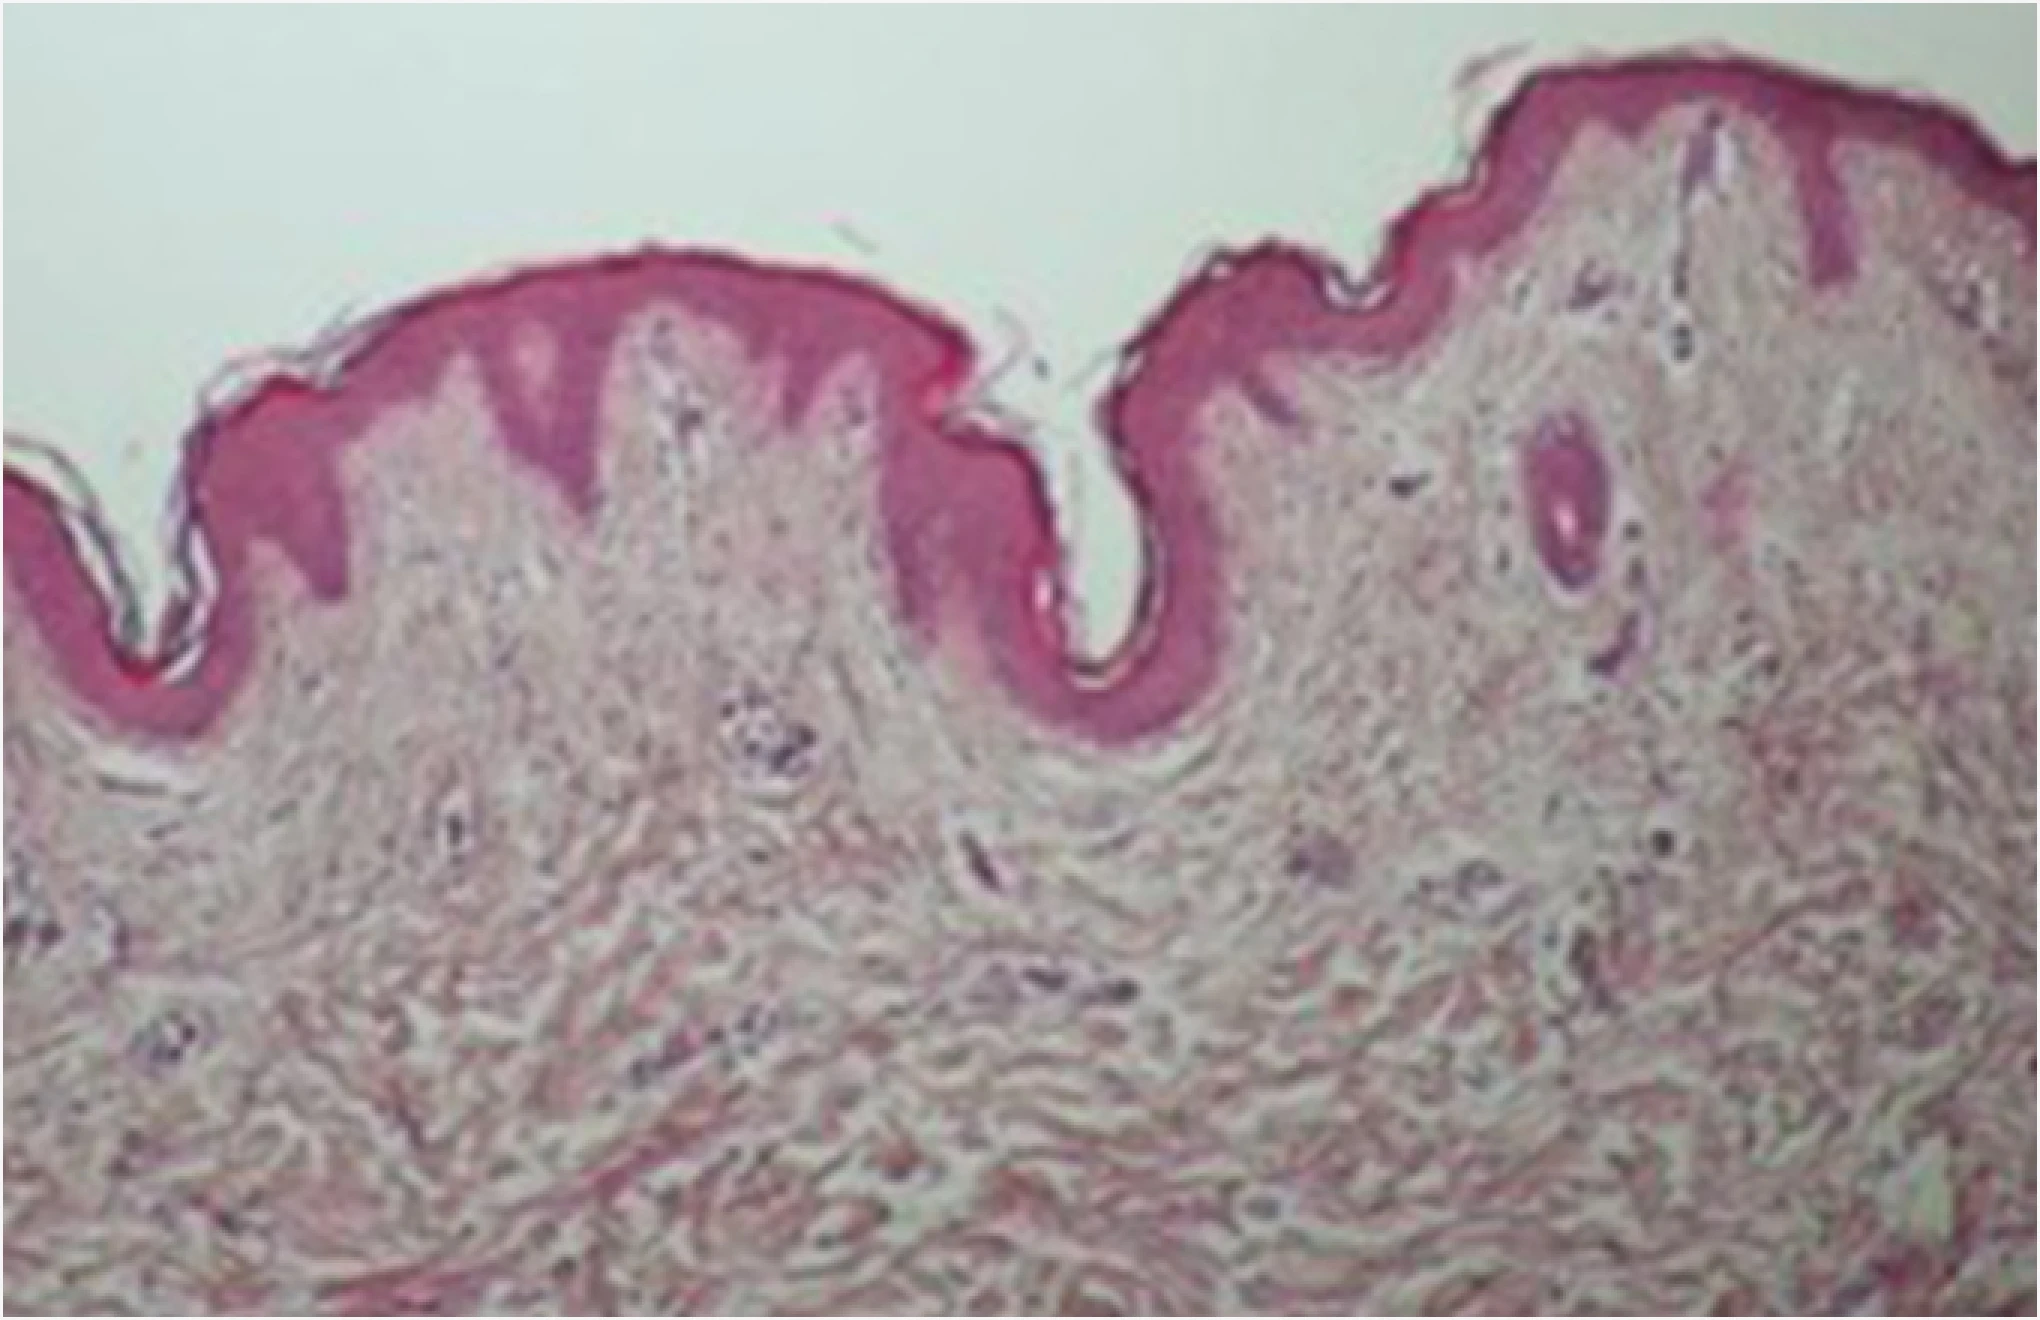

オンダリフト

ONDA施術後、真皮のコラーゲンが活性化されたことが確認できます。

ONDAのエネルギーが熱に変換され、緩んだコラーゲン繊維を収縮させリモデリングを促すことで

スキンタイトニングとリフティング効果が同時に得られることが確認できます。

施術前

施術後